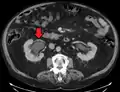

CT scan of bilateral hydronephrosis due to a bladder cancer

Massive hydronephrosis as marked by the arrow.- Renal ultrasonography of hydronephrosis[14]

- Stone causing hydronephrosis[14]